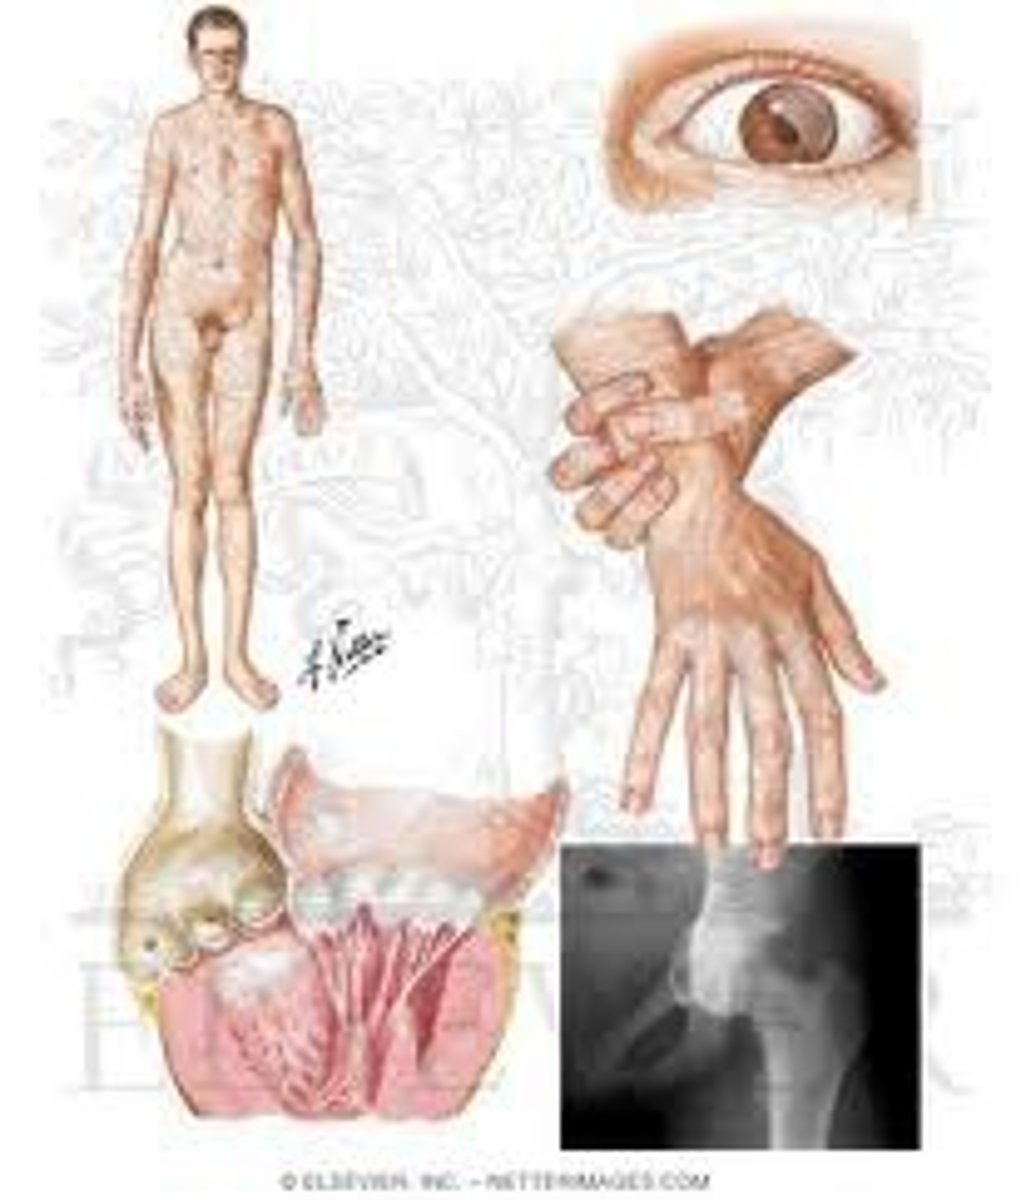

Elastic skin, hyper-mobility of joints, increased bleeding tendency

Ehlers-Danlos syndrome

(type V collagen defect, type III collagen defect seen in vascular ED)

Pro collagen molecules are not cleaved (N/C removal impaired)